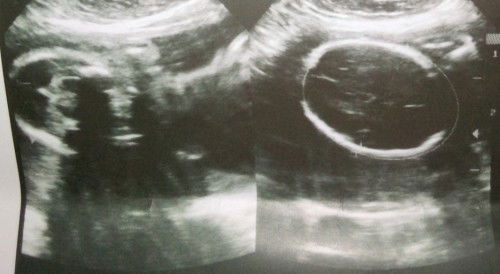

Baby gender

Girl po ba o boy? Satingin nyo po?

Di po kita sa image yung gender mi. Paulit mo na lang sa next scan mo.

Sorry doctor or sonologist lang po makapagsabi para po sure